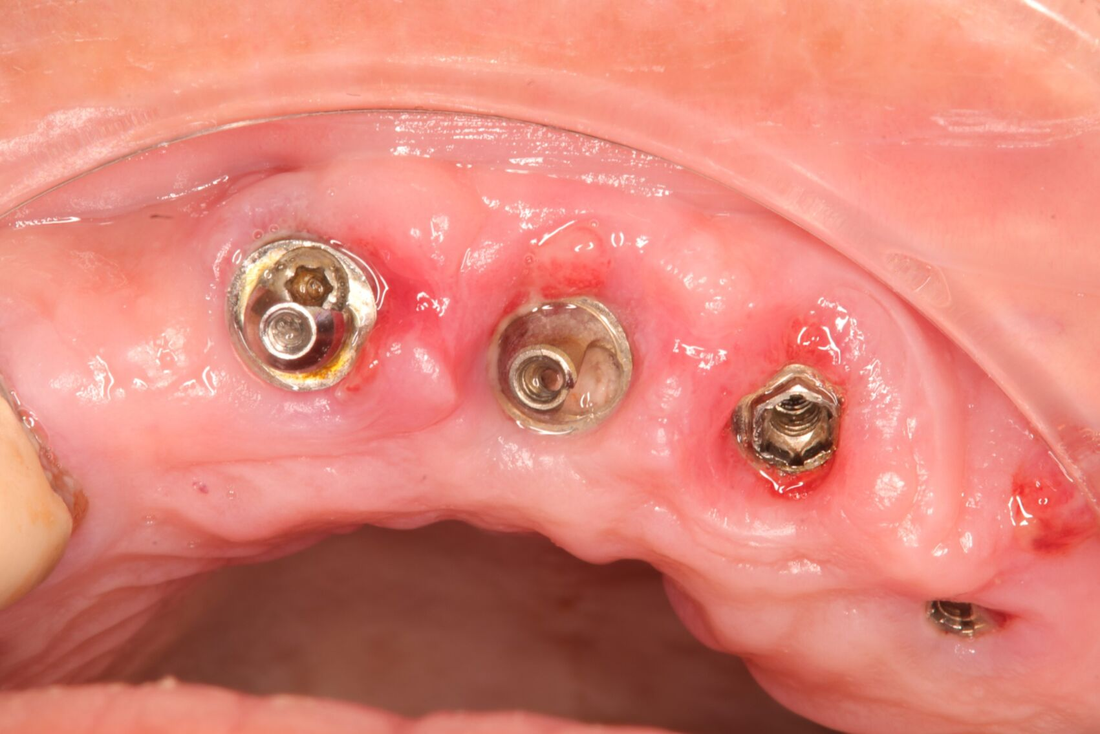

La periimplantitis es una enfermedad inflamatoria crónica que afecta los tejidos que rodean y soportan los implantes dentales.

Se caracteriza por la inflamación de la encía alrededor del implante, pérdida de hueso alveolar y, en casos graves, pérdida del propio implante.

Los signos de periimplantitis pueden incluir enrojecimiento, inflamación y sangrado alrededor del implante, mal aliento, movilidad del implante y sensibilidad.